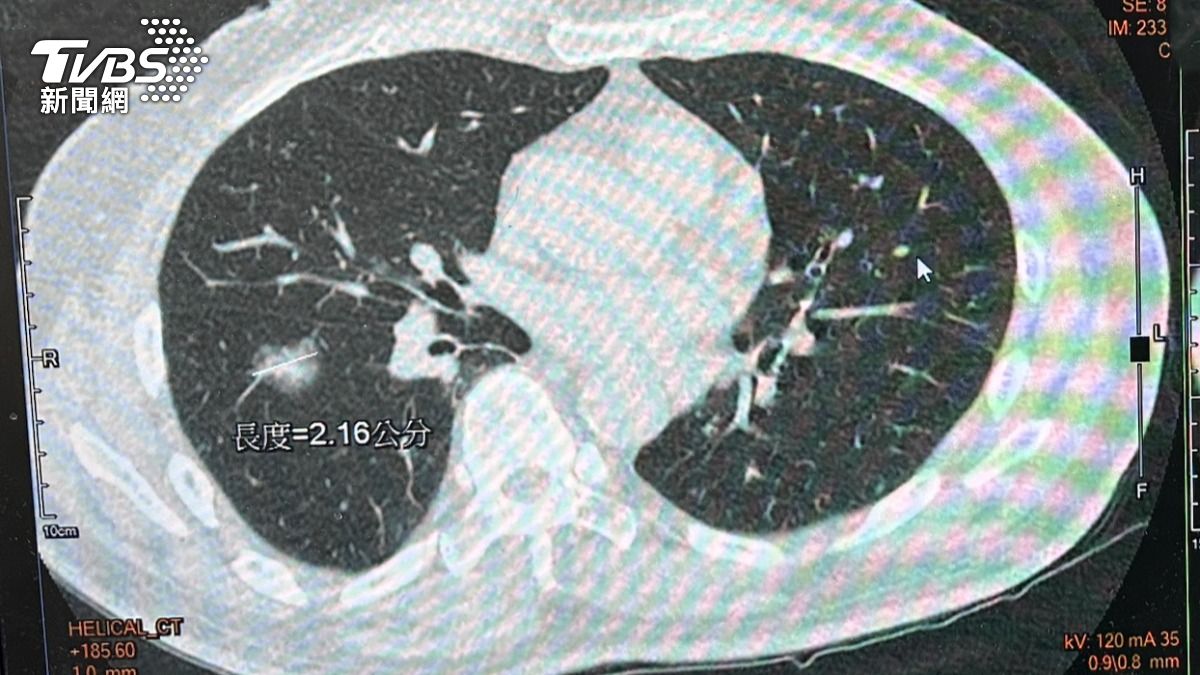

台中市一名64歲的蔡姓男子,平時生活單純,沒有抽菸、不良嗜好,但因為有肺癌家族史,近日仍照往例前往豐原醫院健檢,結果經胸腔外科醫師蕭凱宇檢查,蔡男雙側肺部有10多顆大小不一的肺部結節,評估確診肺腺癌,對此,蕭凱宇也提醒,肺癌早期沒有明顯症狀,,由於肺部缺乏痛覺神經,往往出現血痰、胸痛、胸悶、喘、骨痛、頭痛時,已經是中晚期,五年存活率也將大幅下降。